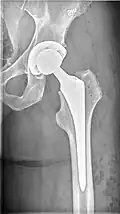

| X-ray of hip with femoral head osteonecrosis | |

ANFH can only be diagnosed by MRI of the hip and X-rays of the hip specifically in the anteroposterior and frog-leg lateral poses.[2] Along with these scans an additional bone scan needs to be done which allows doctors to see the activities of bone cells in a body. Once the images that the physician want are obtained, they are then measured through two systematic reviews.